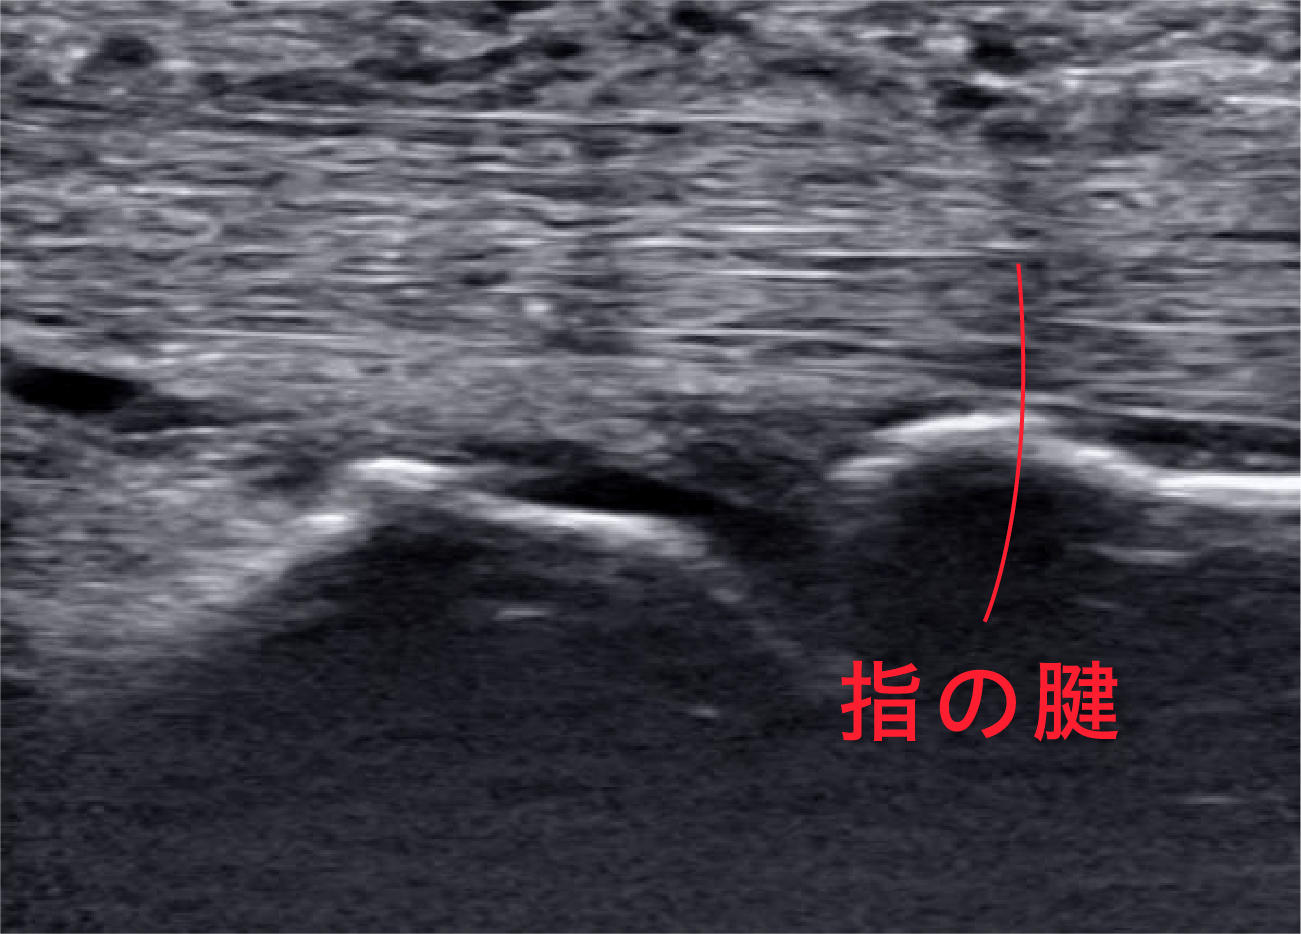

エコーの性能も上がることでこのように綺麗に指の腱が見えるようになりました。